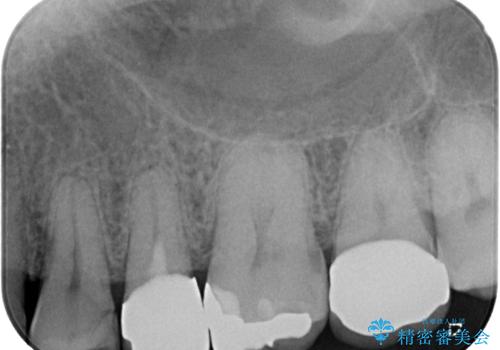

- 歯の間に物が詰まるとのことで来院された患者様です。以前に歯冠部の神経の一部を取り除き、MTAセメントという特殊なセメントを充填し、歯根部の神経を温存する生活歯髄療法(VPT)を行われておりセラミックの詰め物にて修復されていました。セラミックの詰め物が少し欠けたことにより食べ物が挟まってしまう状況でした。

まず神経の生活反応を確認し、今回はセラミックの詰め物のやり替えではなく、セラミックのかぶせ物で治療を行っていくこととしました。

拡大鏡視野下で、セラミックの詰め物、虫歯の除去を行い、オールセラミッククラウンに適した形に整えました。